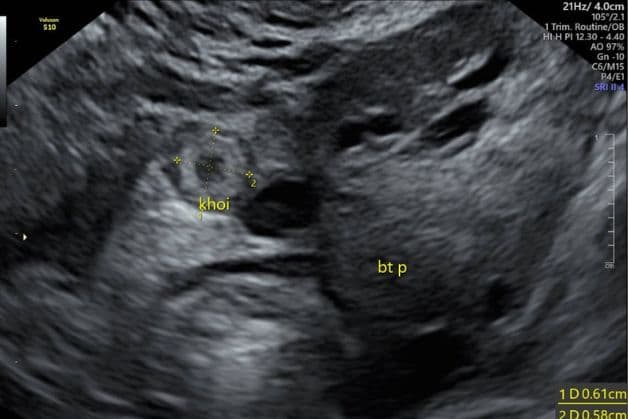

Hình ảnh siêu âm phát hiện thai làm tổ ngoài tử cung

– Siêu âm và xét nghiệm hCG: Siêu âm được sử dụng để xác định vị trí và phát triển của phôi, trong khi xét nghiệm hCG (hormone chorionic gonadotropin) đo mức độ hormone trong máu để xác nhận có thai và theo dõi sự phát triển.